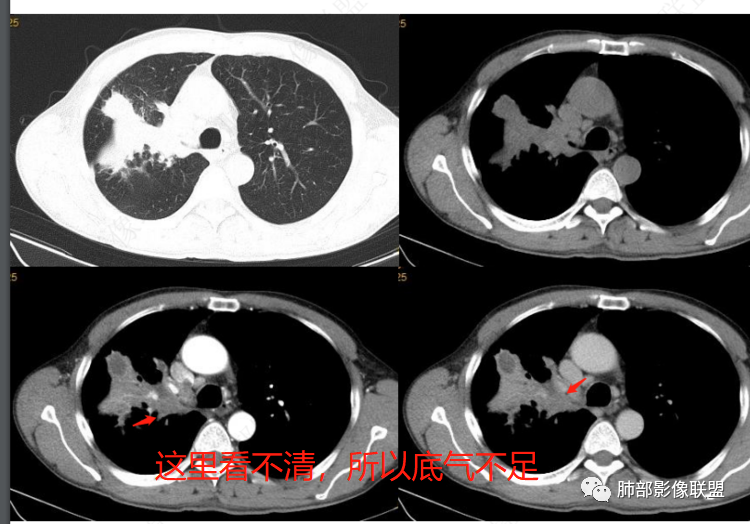

右主支气管阻塞,考虑鳞癌合并阻塞性肺炎可能大

右上肺病灶,右上叶支气管堵塞伴实变,增强后见不均一坏死,血管破坏,考虑恶性可能性大癌肉瘤大于鳞癌。鉴别TB

右主支气管堵塞,伴有实变,内部血管穿行,坏死,考虑鳞癌,鉴别结核、真菌(ABPA)

右肺上叶支气管腔被阻塞,远端肺组织实变,内部密度不均,有斑片状坏死区,个别内部伴有有空洞,周围肺组织伴有阻塞性肺炎改变,增强扫描实变肺呈现明显均匀性强化,内部血管走形自然,坏死区边界清晰!患者有慢性咳嗽咳痰病程,血象高!诊断,慢性肺脓肿合并肺组织机化!鉴别诊断,鳞癌!

支持恶性 右上实变,大肿块,主支气管堵了,增强血管破坏,远侧见片状密度减低坏死区,近侧见小花小草,倾向于鳞癌可能性大,类癌其次,鉴别诊断良性  TB合并感染。

右肺上叶团片影局部膨隆,内见坏死,支气管粘液栓,右主支气管阻塞,阻塞口局部不均匀轻度强化 首先考虑恶性,鳞癌可能,支气管镜检查,除外结核,放线菌等感染性病变。

右肺上叶不规则肿块,沿支气管生长,上叶支气管截断,其内坏死及粘液栓,坏死边界清,远端阻塞改变,不均匀强化,考虑鳞癌,鉴别结核

中年,咳嗽,痰中带血,无发热。影像,右上叶支气管堵塞,常规会首先考虑癌。但是,这个病灶外围大,整个斑片实变明显强化,病灶内似乎能见到支气管走形低密度影,局部坏死边界非常清楚,多数边界有平直边缘,有些层面膨隆,血管走形还可以,无明显推压破坏,不能排除爬行或者OP伴脓肿。支气管镜能搞定诊断

右肺上叶支气管截断,远端肺组织实变,密度不均,有斑片状坏死伴有有空洞,周围肺组织伴有阻塞性肺炎改变,小叶间隔有增厚,增强扫描不均匀强化,内部血管走形自然,坏死区边界清晰!患者有慢性咳嗽咳痰病程,血象高!考虑慢性肺脓肿并机化!鉴别鳞癌!

男,57岁,无诱因咳嗽咳痰,咳黄色粘痰,白细胞增高,CT示右肺上叶实变影,支气管狭窄截断,密度不均匀,增强可见不均匀强化,内部见小空泡伴周边坏死,坏死边界尚清,内部可见血管走行,考虑炎性病变可能,鉴别鳞癌,建议支气管镜镜检。

右上叶不张,右上叶支气管闭塞,断端呈杵状,病变均匀性强化,内可见粘液栓及坏死,静脉期坏死灶及肺门肿大淋巴结有环状强化,急性起病,咳黄痰,白c↑,肿标正常,支气管断端呈杵状,实变均匀强化,可见环状强化的淋巴结,综合分析首选支气管结核,其次鉴别鳞癌

注意截断支气管断面形态

右上叶肺内病灶倒是有炎性特点,坏死区很规则,血管走行比较自然,边缘有模糊的渗出和局部收缩凹陷。

但是,右主支气管堵塞,单这一点就不能排除鳞癌

下一步,支气管镜取活检

中老年男性,主体病灶右肺上叶支气管开口阻塞,呈杯口状,阻塞物强化不明显,致右肺上叶实变不张,见支气管粘液栓(有墨西哥仙人掌特点),另血管束显示清楚,并见坏死及干性空洞,坏死软廊非常清楚,胸膜下炎性反应积液带区,周围见多发小斑片实边,沿支气管血管束分布,胸廊入口右侧不对称,略缩小,炎性肉芽肿,首选TB,支气管镜取材活检,与肺Ca鉴别!

右肺上叶大片实变,密度不均,内见坏死区,边缘膨隆,周围斑片影,气管堵塞,强化不均,坏死区边缘清晰,空洞,考虑鳞癌,肺脓肿。

肺门占位并阻塞性肺炎,粘液栓形成,病灶由内向外,定位支气管来源肿瘤性病变,考虑鳞癌,鉴别:腺样囊性癌、结核等。

右肺上叶实变影,边缘膨隆,粘液栓形成,支气管阻塞,不均匀强化,考虑鳞癌,鉴别结核。

我说一下征象,判断这类病变,首先应该考虑:炎性、恶性肿瘤

如果没把握,我们就从恶性出手。

恶性这类分析思路:整个是肿瘤?腔内肿瘤?

肺动脉走形自然

如果近端中央型肺癌,肺动脉破坏明显——所以晨读病例不支持中央型肺癌。

下图:这是中央型肺癌的特点:肺动脉破坏。

腔内肿瘤?肺动脉没有推移,累及多段

远端不是阻塞性不张,不支持腔内肿瘤

然后就是外朝内肺炎型肺癌或者炎性

远端支气管是通畅的,只是腔内粘液栓